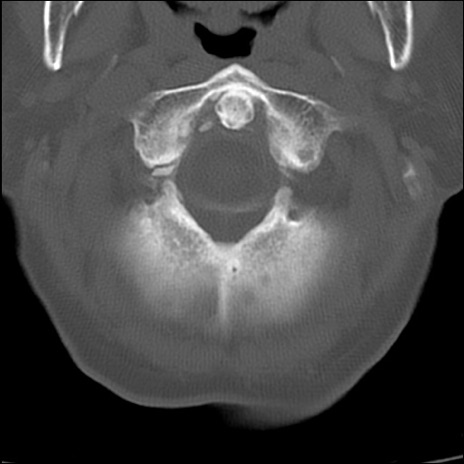

症例48 頚椎CT(横断像)

頚椎CT